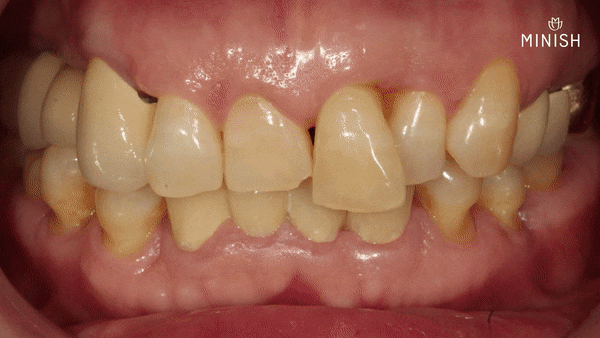

평생을 괴롭힌 돌출된 앞니, 단 하루 만에 벗어났습니다.

튀어나온 치아가 교정이나 과한 삭제 없이도 달라질 수 있다는 사실, 처음엔 쉽게 믿기 어려울 수도 있습니다. 하지만 짧은 시간 안에 눈에 띄는 변화가 있었고, 동시에 구강 건강까지 회복되었기에 그 변화는 더 특별했습니다.

미니쉬는 불필요한 손상 없이 돌출된 치아의 불균형을 조정합니다. 신경을 건드리지 않고, 자연스러운 비율과 대칭을 맞추는 방식으로 배열을 안정시킬 수 있습니다. 무리한 치아 손상 없이도 가지런한 형태를 완성할 수 있다는 것, 그것이 미니쉬의 핵심입니다.

지금의 평택엄마는 더 이상 앞니 때문에 웃음을 숨기지 않습니다. 거울을 볼 때마다 느끼는 만족감은 그동안의 고민을 단숨에 잊게 만들었습니다. 치아는 스스로 회복되지 않으며 외부적인 개입 없이 재생되기도 어렵습니다. 그렇기에 어떤 방식으로 다룰 것인지는 신중하게 고민해야 합니다. 무엇보다 중요한 건 ‘콤플렉스 해소’뿐 아니라 건강을 지키는 선택이 되어야 한다는 점입니다.